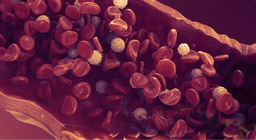

The blood is considered a fluid connective tissue that connects various regions of the body.

Blood is circulated by the heart in a closed circuit through vessels.

Blood is circulated by the continuous pump function of the heart inside a closed system.